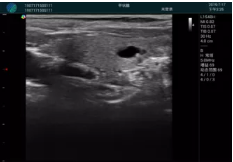

清晰顯示腺體內低回聲快影,邊界清晰,包膜較光滑

確定進針路徑并實時監(jiān)測抽吸針與腫塊位置關系

抽吸針進入腫塊內部進行旋切

抽吸過程中可見腫塊明顯縮小,并根據腫塊位置改變針道位置

抽吸旋切后再進行超聲復查,原腫塊區(qū)域未見殘留組織及出血